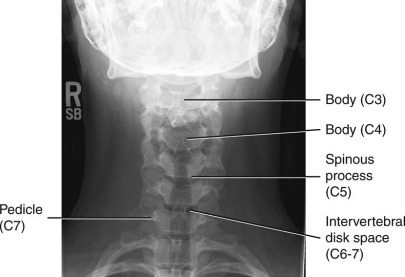

AP Axial C-Spine: Eval Criteria

Angle CR 15 to 20 degree cephalad neck extended slightly

C3 to T2 demoed

Space between pedicles and intervertebral disk spaces clearly seen

Mandible and base of the skull should superimpose C1-2